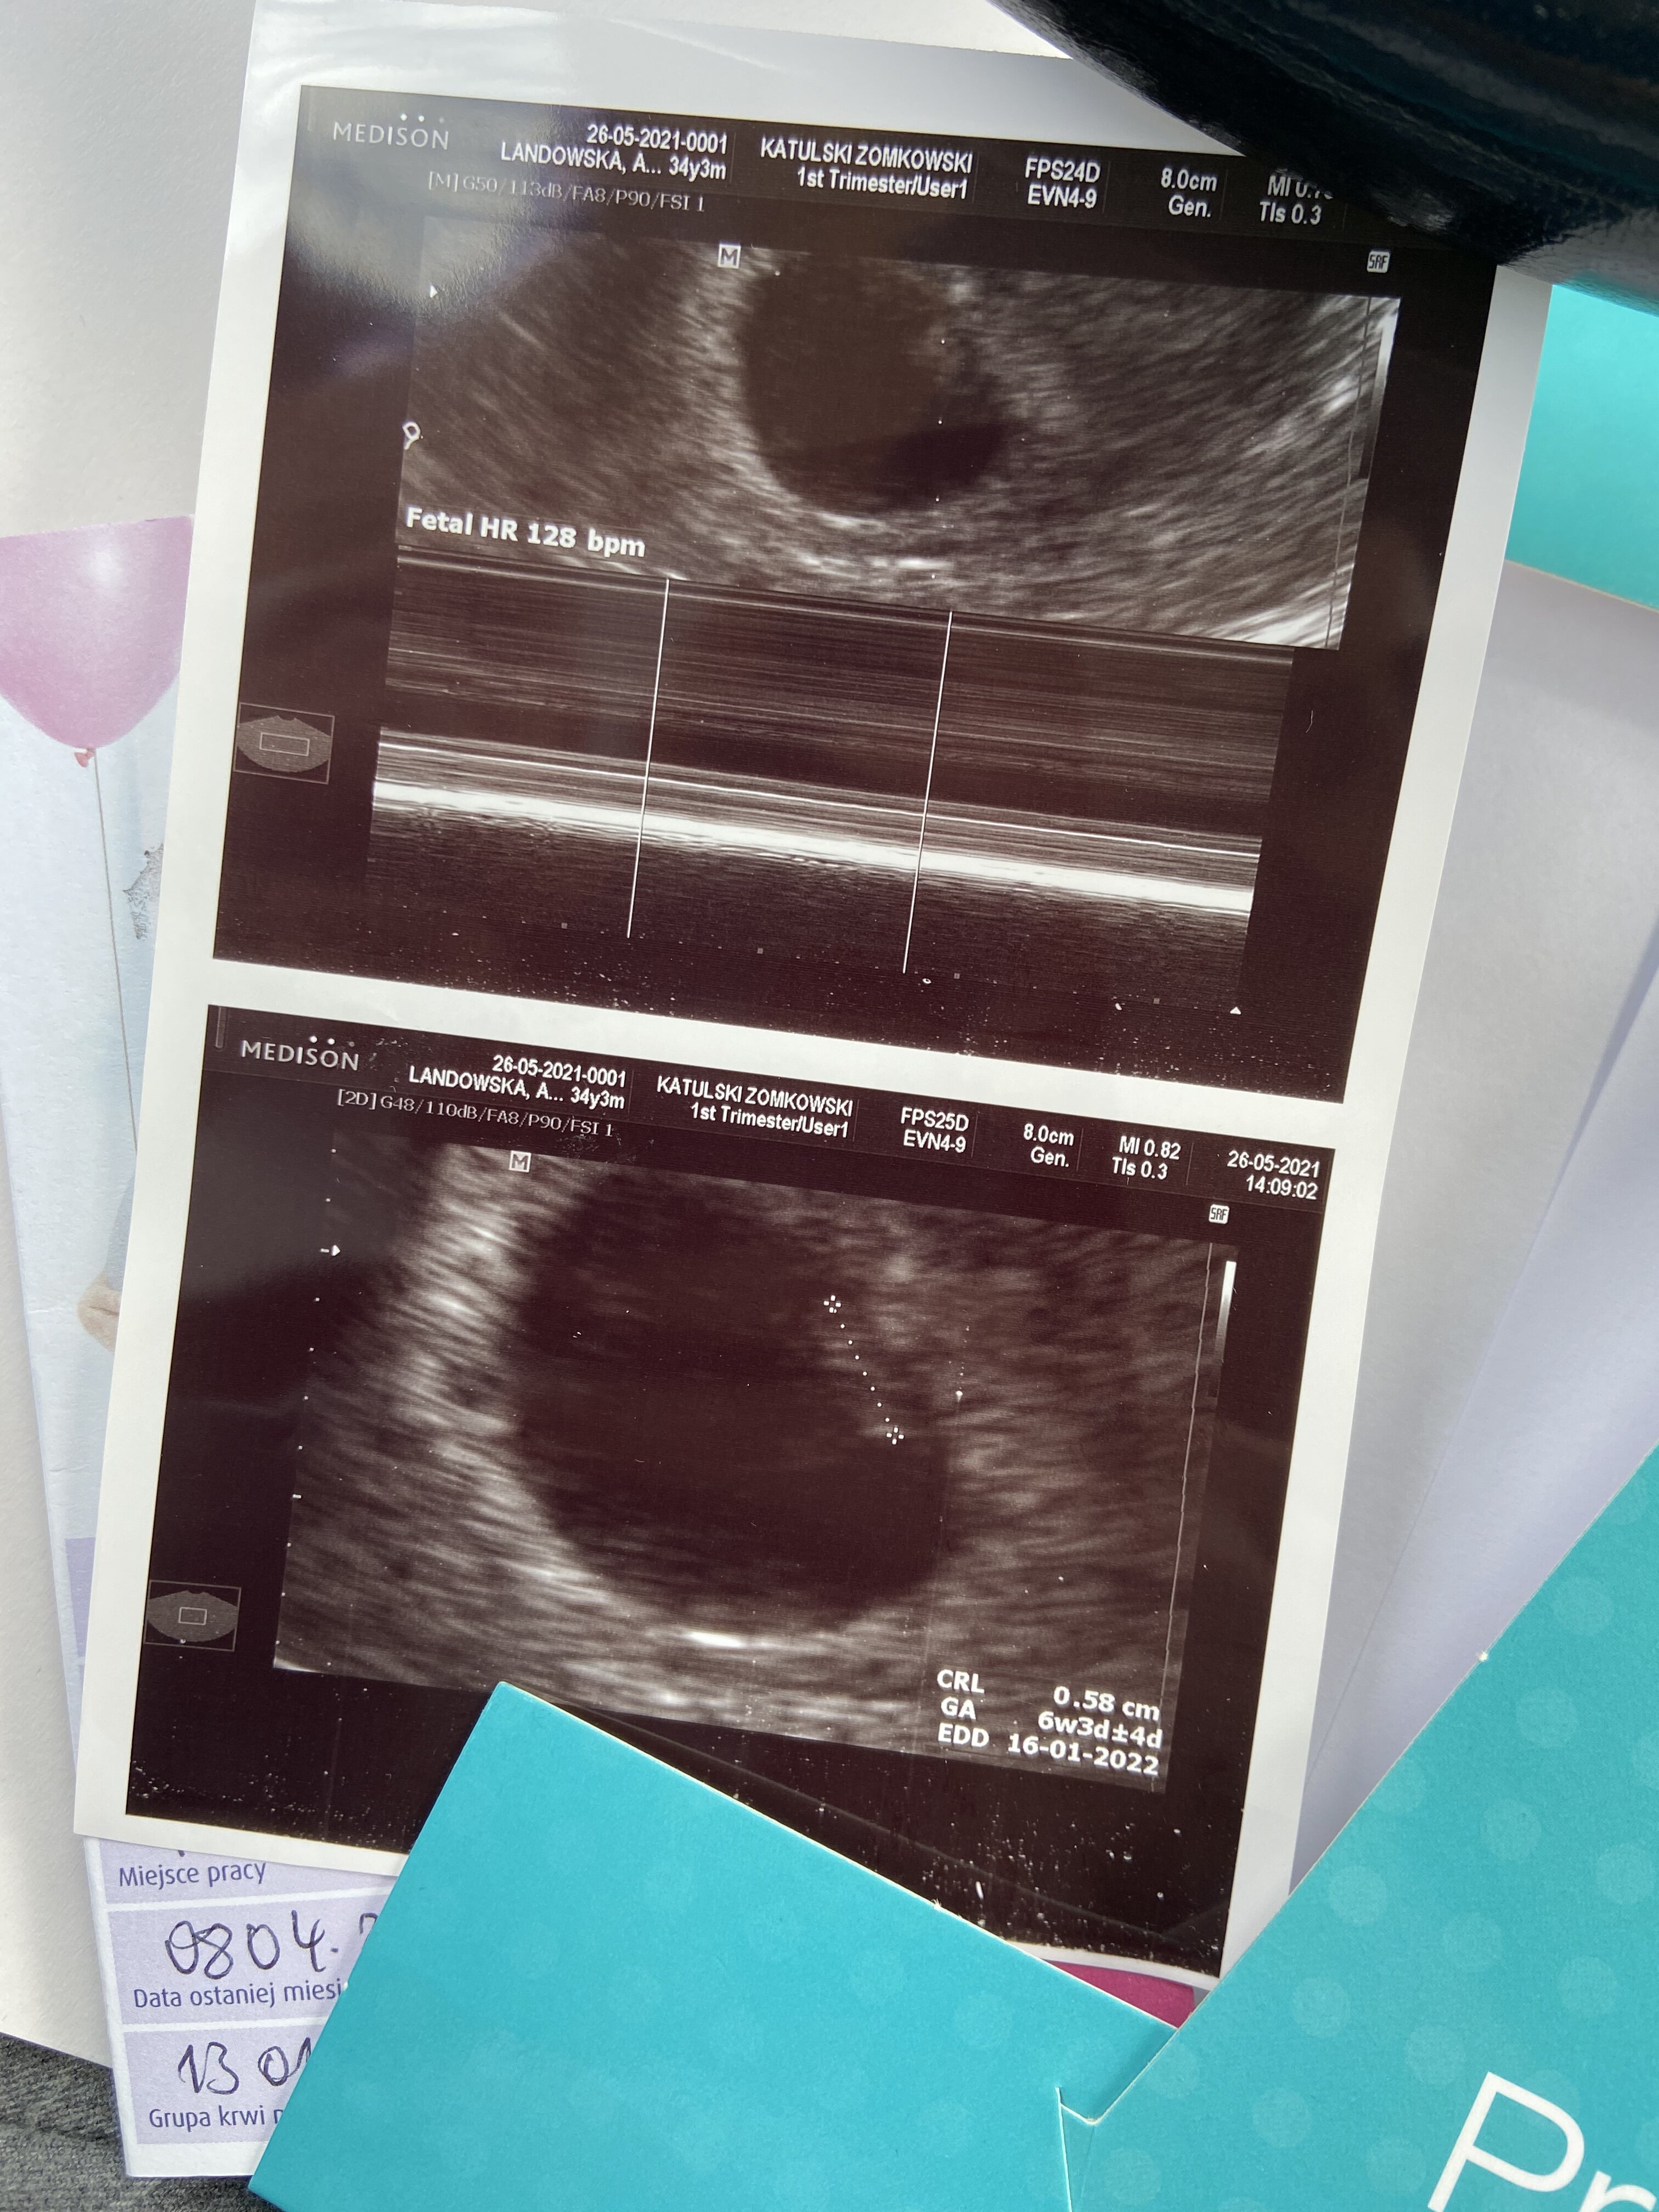

Hej dziewczyny, ja po wizycie, na ten moment wszystko ok, serduszko bije :) co mnie zaniepokoilo, a zobaczyłam dopiero w domu-Zarodek ma 8 mm, a pecherzyk ciazowy aż 27 mm. Lekarz nic o tym nie wspominał, ale to chyba za dużo. Dacie radę sprawdzić jakiej wielkości były Wasze pecherzyki i zarodki w okolicy 6+5? Będę wdzięczna! :)

U mnie było tak w 6+3

Załączniki

• B7312D4F-5D5C-4C15-A67B-AB0216C061CE.jpeg

B7312D4F-5D5C-4C15-A67B-AB0216C061CE.jpeg

1,5 MB · Wyświetleń: 120